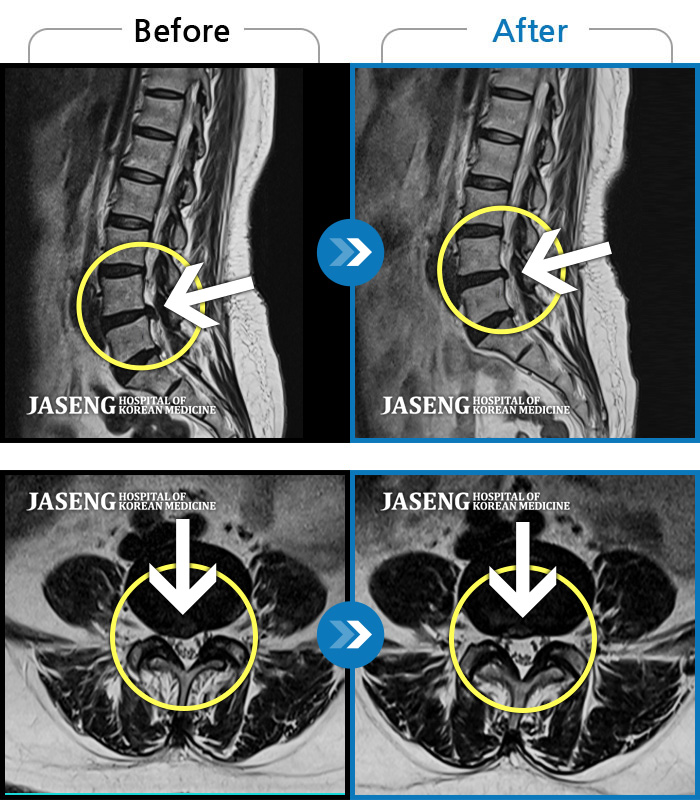

허리디스크

광주 · 김동은 원장

허리 양측 둔부에서 발가락으로 통증, 비증, 힘이 빠지는 증상

촬영시기

2018.08.11 ~ 2019.03.27

2019.04.25